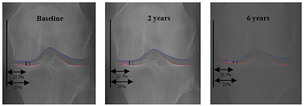

AI가 무릎 골관절염 '가장 닳은 지점' 찾는다…새 영상 지표 제안

인공지능(AI)을 활용해 무릎 관절에서 연골이 가장 많이 닳은 지점을 자동으로 찾아내는 새로운 영상 평가 지표가 제시됐다. 기존처럼 정해진 위치에서 관절 간격을 측정하는 방식보다 환자마다 ...